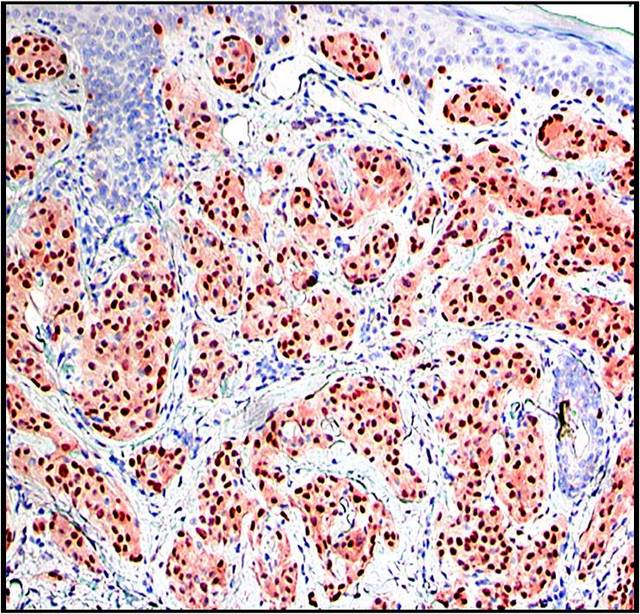

Microscopic (histologic) description

- Cellular, myxoid or mixed subtypes

- Involves dermis or subcutis

- Multinodular mass with myxoid matrix and peripheral fibrosis

- Whorled or focally fascicular patterns of spindled and epithelioid mononuclear cells with abundant cytoplasm, indistinct cell borders

- Margins usually positive; usually occasional multinucleated giant cells

- Variable nuclear atypia

- Median 4 MF / 25 HPF, may have 10+ MF / 25 HPF, may be atypical

Microscopic (histologic) images